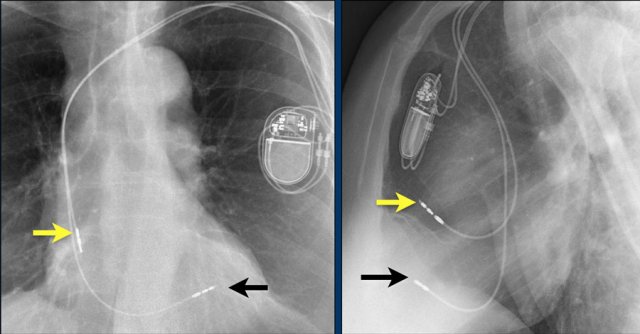

Here a patient with a normally placed ICD on the left image.

Months later there was malfunction due to ICD box and lead rotation (yellow arrow) and retraction (white arrow).

Here another patient with the Twiddler's syndrome.

Notice curling of the lead near the pacemaker and at the tip in the right ventricle (arrows).